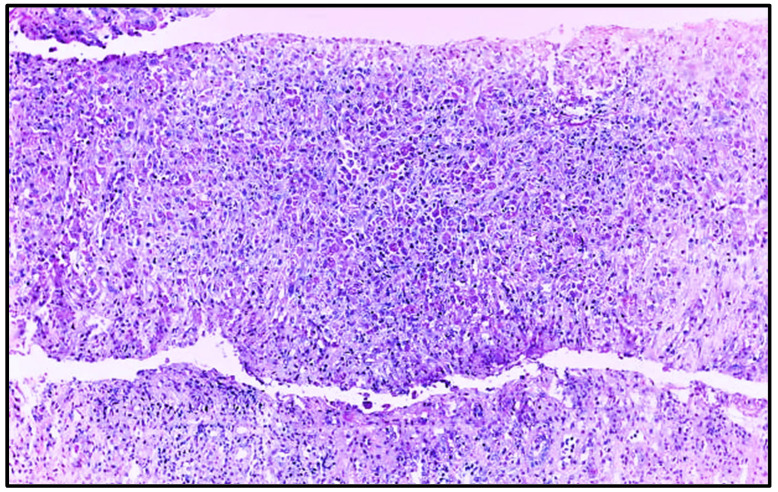

摘要:肾斑疹是一种罕见的慢性肉芽肿性疾病,常伴有免疫抑制和持续的革兰氏阴性感染,尤其是大肠杆菌。病例介绍:我们报告一例31岁女性高血压,妊娠期糖尿病,引产后子宫刮除为先兆子痫在23周。术后出现尿脓毒症。影像学显示双侧肾肥大,实验室检查显示急性肾损伤(KDIGO III期)、贫血和血小板减少症。血液和尿液培养培养出大肠杆菌。肾活检证实斑疹,显示pas阳性Michaelis-Gutmann小体和Von Hansemann细胞。患者对长期抗生素治疗和支持性护理有反应。讨论与结论:本病例强调了在非典型尿路感染和肾脏病患者中考虑肾脏畸形的重要性,特别是在产科环境中。组织病理学确认是必要的,及时使用细胞内活性抗生素治疗可导致良好的结果。早期诊断对预防不可逆肾损害至关重要。

Introduction: Renal malacoplakia is a rare chronic granulomatous disease, often associated with immunosuppression and persistent Gram-negative infections, particularly Escherichia coli. Case Presentation: We present a case involving a 31-year-old woman with hypertension, gestational diabetes, and prior uterine curettage after labor induction for preeclampsia at 23 weeks. She developed urinary sepsis post-procedure. Imaging revealed bilateral nephromegaly, while laboratory tests showed acute kidney injury (KDIGO stage III), anemia, and thrombocytopenia. Blood and urine cultures grew Escherichia coli. Renal biopsy confirmed malacoplakia, demonstrating PAS-positive Michaelis-Gutmann bodies and Von Hansemann cells. The patient responded to prolonged antibiotic therapy and supportive care. Discussion and Conclusion: This case highlights the importance of considering renal malacoplakia in patients with atypical urinary tract infections and nephromegaly, particularly in obstetric settings. Histopathological confirmation is essential, and timely treatment with intracellularly active antibiotics can lead to favorable outcomes. Early diagnosis is critical to prevent irreversible renal damage.